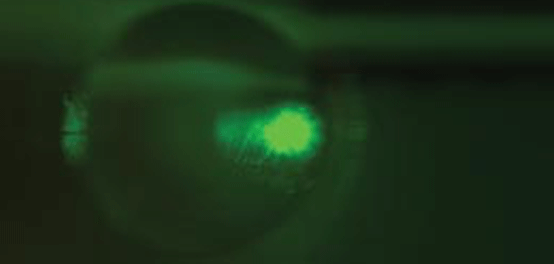

Discovering DIC Microscopy

Join Stefaan Vandendriessche, Sales and Applications Engineer, as he demonstrates a Differential Interference Contrast (DIC) microscope built from stock components found in the Edmund Optics catalog.